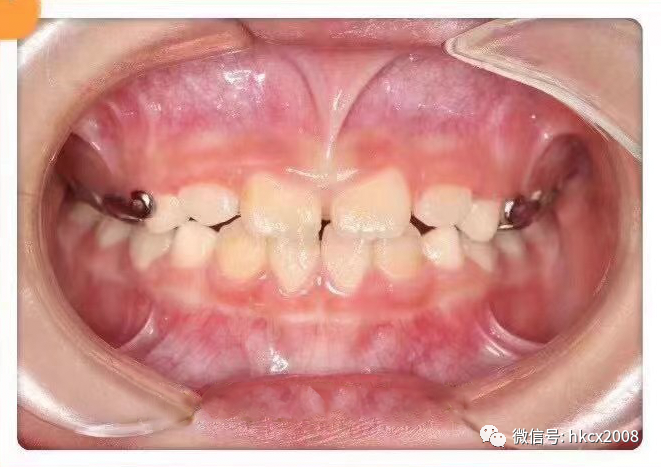

图片

矫治后

最佳治疗年龄:3-5岁,由于这时候恒牙还没出现,乳牙牙根还没消失,一般只需要佩戴活动矫治器、纠正不良的口腔习惯,3-6个月就可以治好。如果超过这个年龄也没关系,越早治疗越不容易“受罪”。